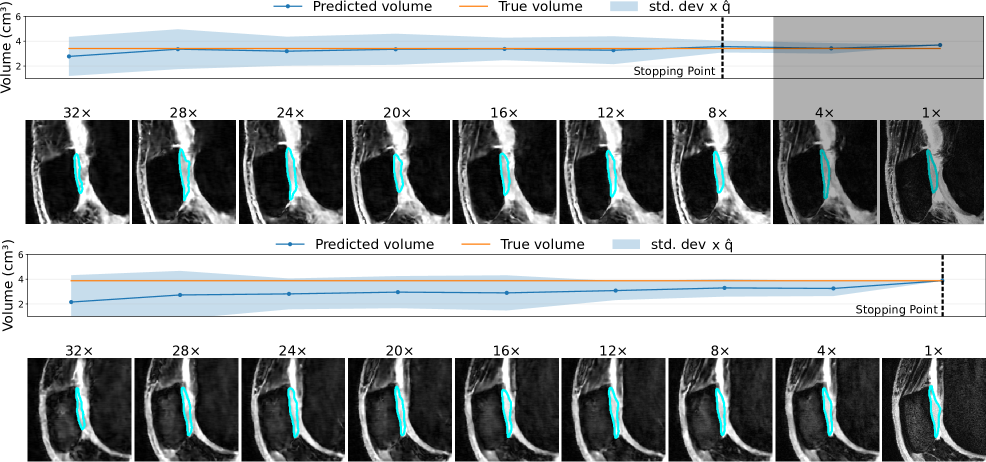

4.3 Qualitative Results

To provide a qualitative understanding of our dynamic stopping mechanism, Figures 4 and 5 show representative cases of both early and late scan terminations. Each figure visualizes the evolution of the reconstruction, segmentation, and the downstream metric along with its calibrated uncertainty as more k-space data is acquired. As expected, we observe a consistent trend across all examples: as the acquisition progresses, reconstruction quality and segmentation accuracy visibly improve. Moreover, the prediction uncertainty decreases the more k-space data is being collected. Additional reconstruction examples are displayed in Figure 6 and 7. Concurrently, the downstream metric estimation converges toward the ground truth value while the corresponding uncertainty bands narrow. Crucially, instances of high uncertainty consistently correspond to visible artifacts, segmentation errors, and larger deviations in the final metric, confirming that our uncertainty estimates effectively track acquisition quality.

The core contribution of this work lies in the dynamic stopping mechanism. The dramatic difference between uncalibrated and calibrated stopping points (Figure 3) reveals a critical insight: raw neural network uncertainties are not reliable proxies for model error. The uncalibrated models were consistently overconfident, terminating scans when the downstream metric error was still high (Figure 3). This misalignment poses a significant clinical risk. Conformal calibration corrects this by widening the uncertainty intervals to better reflect the true potential for error, leading to more appropriate and safer stopping decisions. This finding aligns with a growing body of literature emphasizing the necessity of calibration for deploying machine learning models in high-stakes medical applications [26, 41].

Furthermore, our qualitative results (Figures 4, 5) visually corroborate these quantitative findings. The clear correlation between wider uncertainty bands, visible image artifacts, and inaccurate segmentations provides intuitive evidence that the calibrated uncertainty is a meaningful and trustworthy indicator of quality.